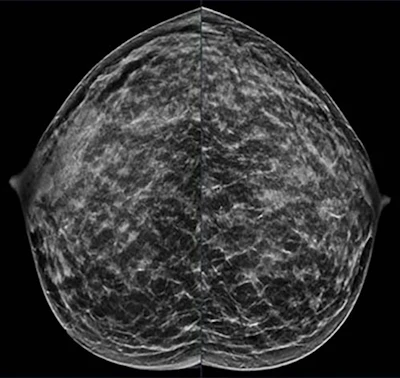

A 40-year-old patient presents for routine screening with a family history of the paternal grandmother, age 55. Extremely dense breast tissue is noted on mammography right and left craniocaudal view.RSNA

A 40-year-old patient presents for routine screening with a family history of the paternal grandmother, age 55. Extremely dense breast tissue is noted on mammography right and left craniocaudal view.RSNA